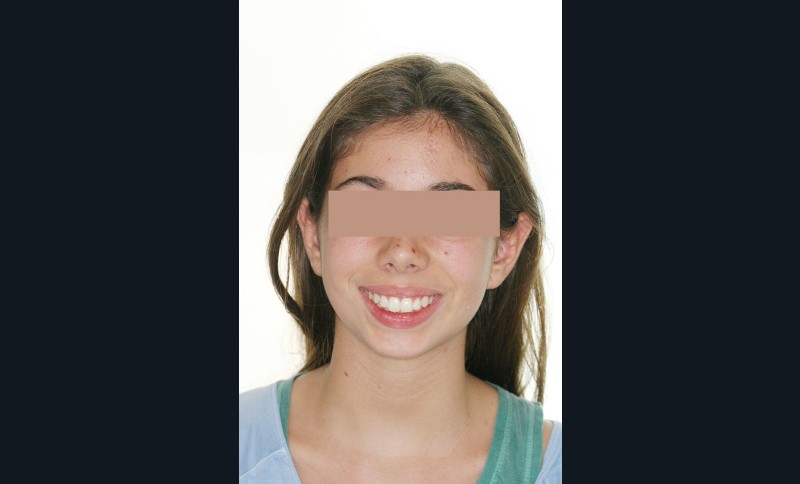

Nous sommes en présence d’une patiente adolescente âgée de 12 ans ½ dans une phase de croissance faciale favorable.

Elle présente une classe II squelettique par rétrognathie mandibulaire et une classe II dentaire molaire et canine droite et gauche associée à une biproalvéolie incisive maxillaire et mandibulaire.

Le pronostic de correction de la classe II est favorable mais il est très important de souligner la vestibuloversion incisive mandibulaire et le risque parodontal associé (fig. 1 à 3).